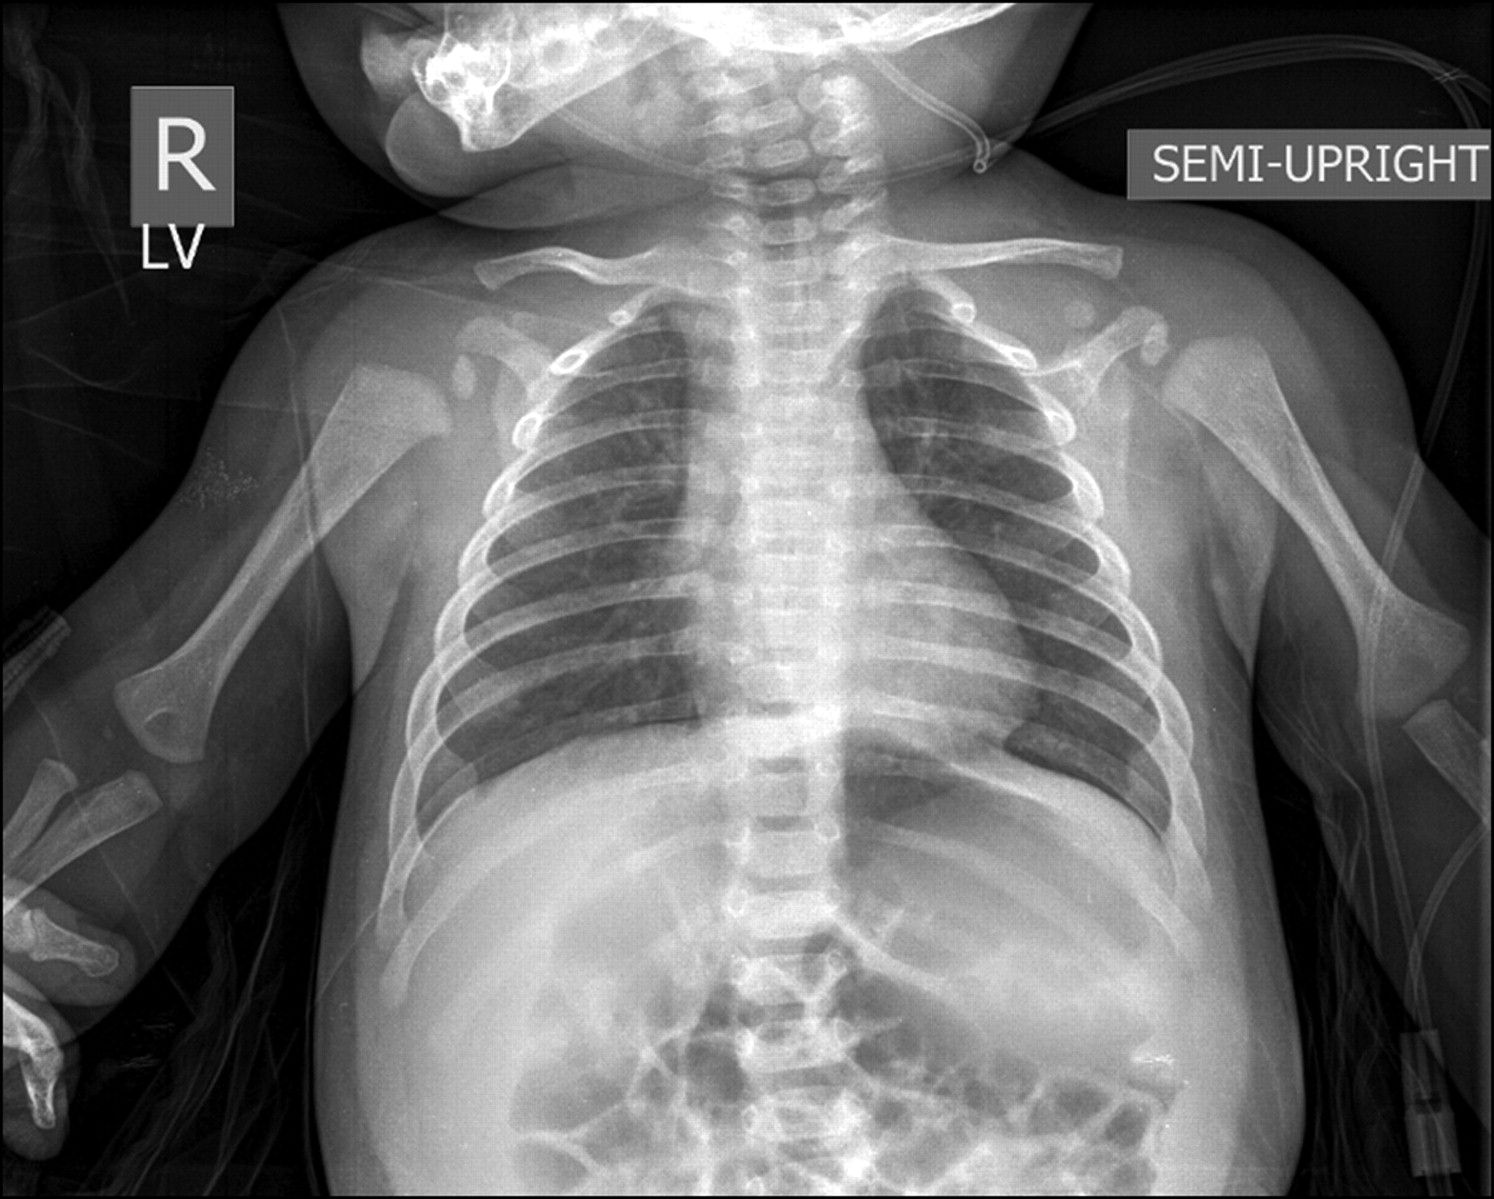

Komplikasi yang muncul karena penyakit bronkiolitis